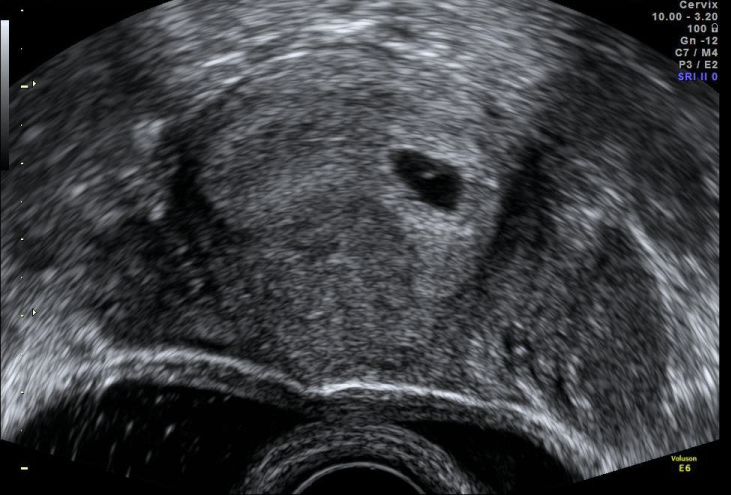

At discharge, the patient was fully clinically recovered, with normal inflammatory values. At ultrasound, there was the same heterogeneous right adnexal mass with four cm of largest diameter (Figure 2) and no fluid at the Douglas Pouch and an intrauterine gestational sac with yolk sac (Figure 3).

Figure 3: Intrauterine gestational sac with yolk sac inside. View Figure 3